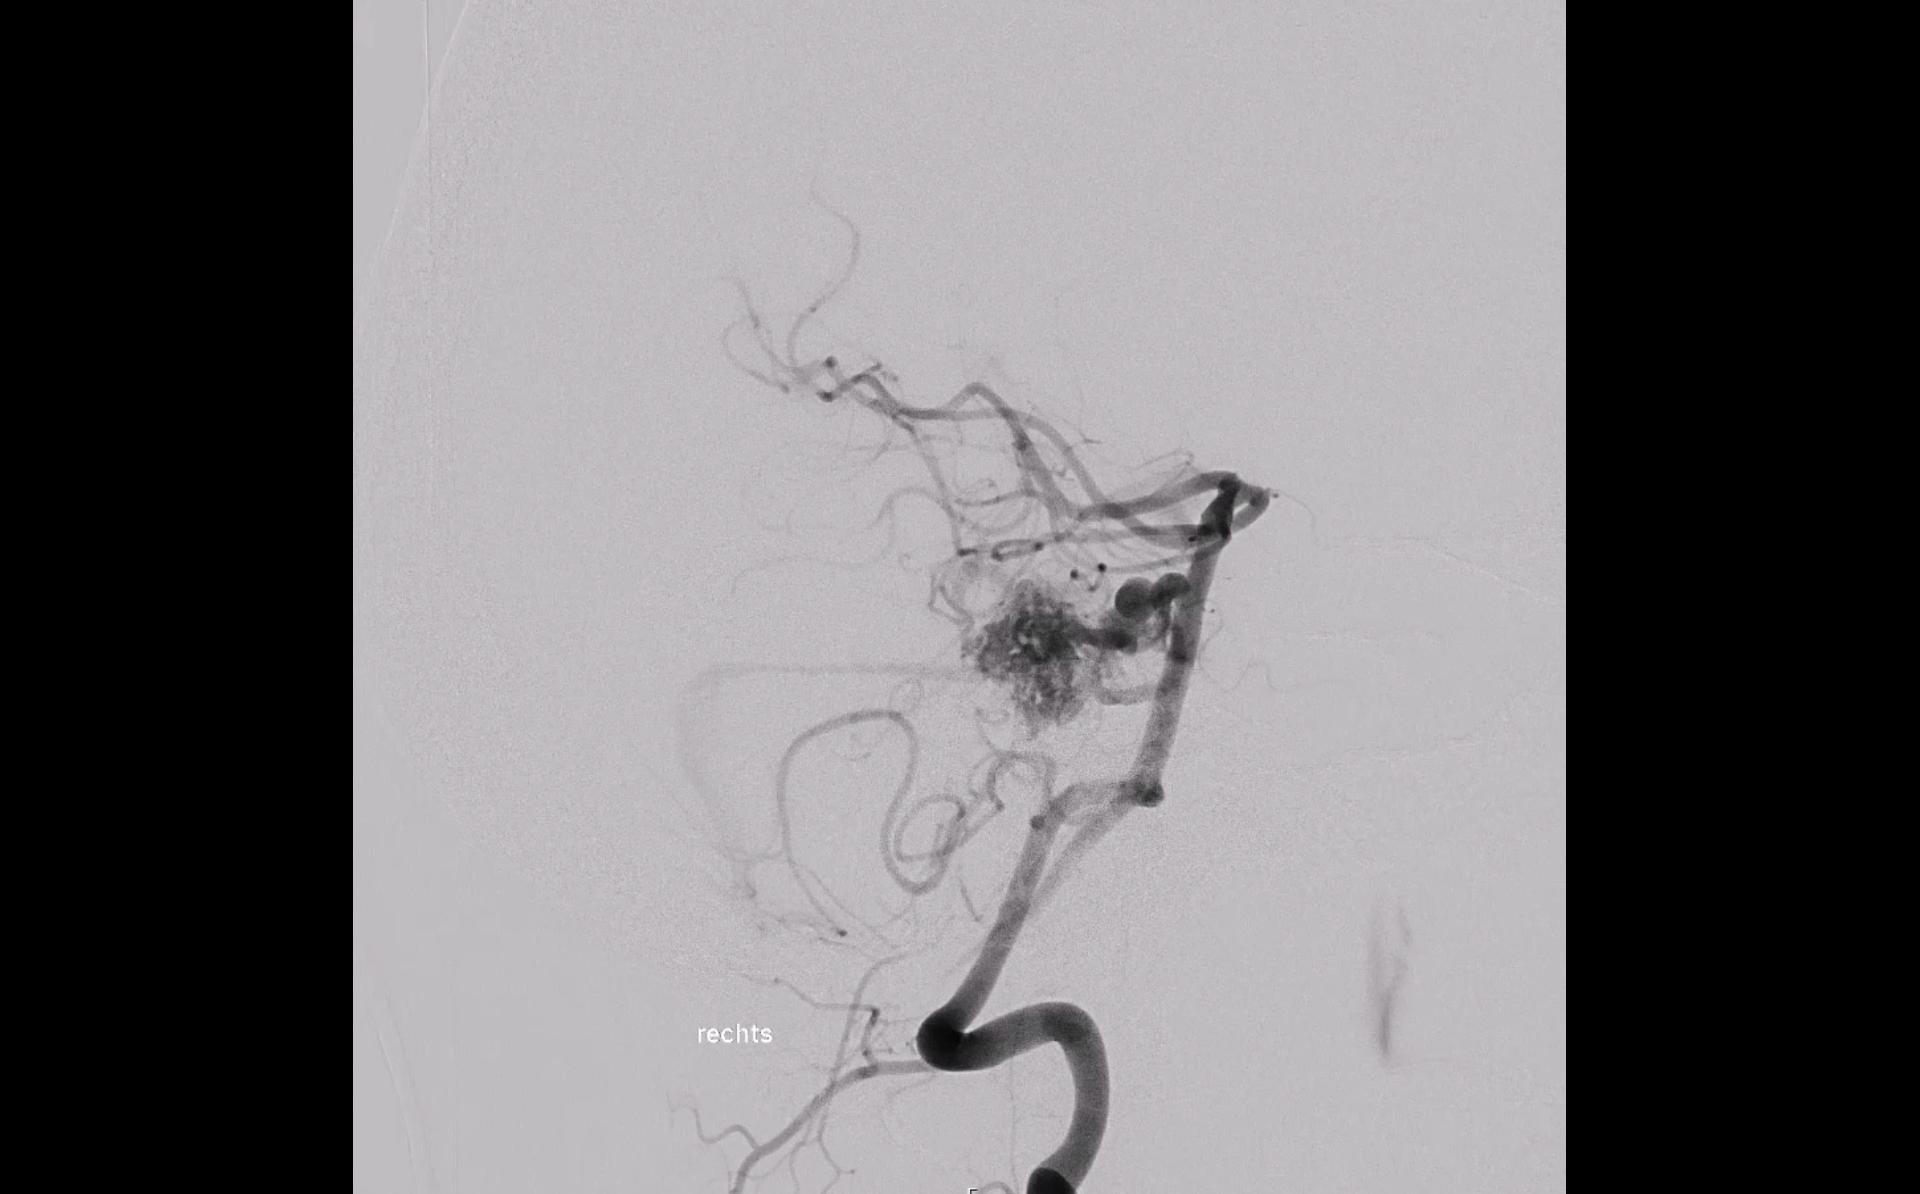

Intranidales Aneurysma

Unter einem intranidalem Aneurysma versteht man ein Aneurysma, welches sich im Nidus einer AVM befindet. Das vorhandensein eines intranidalen Aneurysma erhöht das Blutungsrisiko einer AVM[^1].

Der Goldstandard in der Beurteilung einer AVM und einem damit assoziierten intranidalen Aneurysmas ist die digitale Subtraktionsangiographie (DSA). Charakteristischerweise füllt sich ein intranidales Aneurysma früh in der DSA[^1].

- Angiographie einer Arteriovenöse Malformation mit einem assoziierten intranidalen Aneurysma.